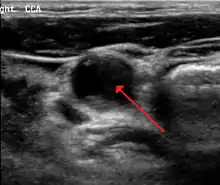

Carotid artery stenosis is usually diagnosed by color flow duplex ultrasound scan of the carotid arteries in the neck. This involves no radiation, no needles and no contrast agents that may cause allergic reactions. This test has good sensitivity and specificity.[11]

Typically duplex ultrasound scan is the only investigation required for decision making in carotid stenosis as it is widely available and rapidly performed. However, further imaging can be required if the stenosis is not near the bifurcation of the carotid artery.